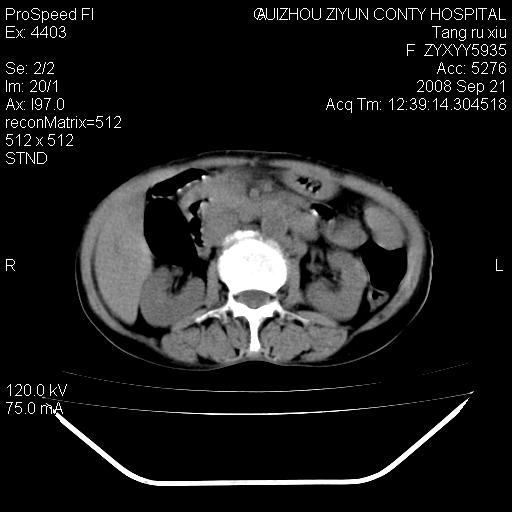

f、57岁,上腹痛.2月,近来胸闷。2月前在外院摄胸片示左侧胸腔少量积液。

(患者腹痛入院,欲吐,临床医生说禁饮,所以没有口服对比剂)

肝脏大小形态尚可,其实质内可见多发大小不等的低密度影,边缘模糊。肝门区结构紊乱,腔静脉腹主动脉旁可见多发软组织密度影,部分融合成团块状,并向下延伸。胰腺及十二指肠结构显示不清。腹腔内脐后肠管走形僵硬,管壁可见增厚。盆腔内可见多个淋巴结影。所扫层面左侧胸腔可见大量弧形水样密度影,其内侧可见被压缩的肺组织影。左侧胸壁可见一小结节样软组织密度影,边缘模糊。心脏纵隔向右侧移位。心脏包膜内可见囊样低密度影,其内侧心房室周围可见一圈气体样密度影。纵隔内大血管旁可见多发软组织团块影,部分融合。

1.腹膜后淋巴瘤侵及肝脏,肺内及纵隔内多发转移。2.左侧大量胸腔积液并压缩性肺不张。3.心包脓肿可能,转移不除外。4.脐后局部肠管管壁增厚,考虑炎症可能,肿瘤不除外。